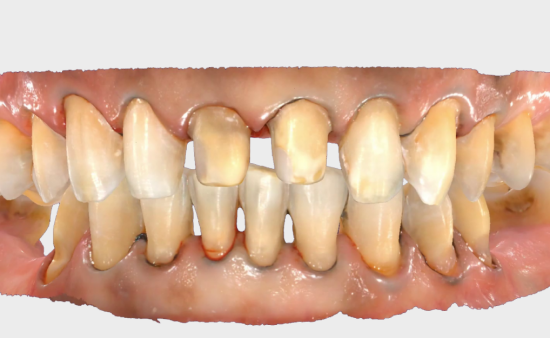

Step 1: Data Collection

• For ceramic veneers, it is advisable to use minimal tooth structure reduction with a minimally invasive approach.

812123b0-ff5f-8722-a006-b54362345bb4_副本.png

• A digitally guided veneer preparation workflow ensures precise tooth reduction by using CAD software to calculate the minimal thickness needed for the final veneers.